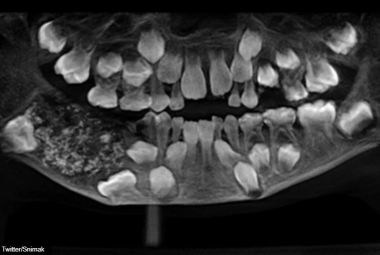

Zubar iz usta sedmogodišnjeg dječaka izvadio 526 zuba